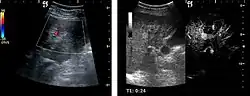

Benign focal nodular hyperplasia (CEUS). Gray scale examination (left) detects the lesion. CEUS examination (right) allows characterization of tumor nature based on central contrast enhancement and centrifugal dispersion.

It is a tumor developed secondary to a circulatory abnormality with abundant arterial vessels having a characteristic location in the center of the tumor, within a fibrotic scar. A radial vessels network develops from this level with peripheral orientation. The tumor's circulatory bed is rich in microcirculatory and portal venous elements. The incidence is higher in younger women and tumor development is accelerated by oral contraceptives intake. 2D ultrasound appearance is a fairly well-defined mass, with variable sizes, usually single, solid consistency with inhomogeneous structure. Rarely the central scar can be distinguished. Spectral Doppler examination detects central arterial vessels and CFM exploration reveals their radial position. CEUS examination shows central tumor filling of the circulatory bed during arterial phase and completely enhancement during portal venous phase. During this phase the center of the lesion becomes hypoechoic, enhancing the tumor scar. During the late phase the tumor remains isoechoic to the liver, which strengthens the diagnosis of benign lesion.